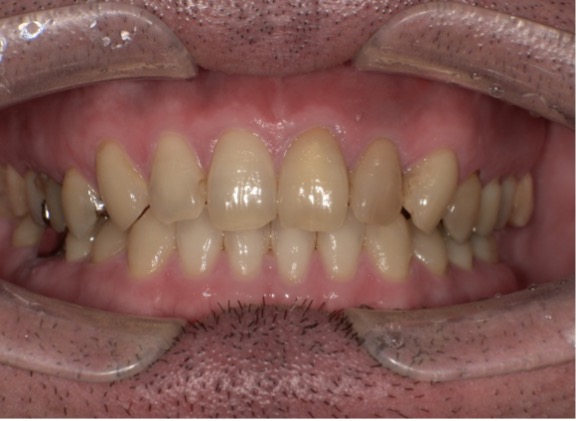

【Before】

【After】

インプラントを左右の奥歯に入れたことで左右のバランスが良くなり、前歯の噛み合わせも改善されたことで全体的に調和の取れた噛み合わせをつくる事ができました。